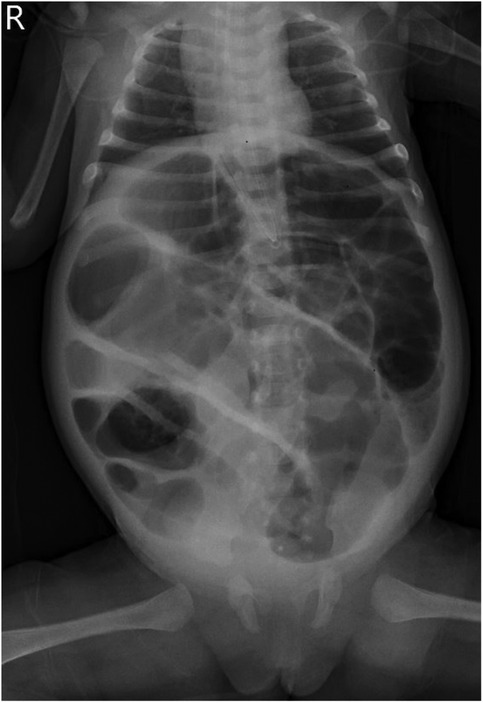

Primary Segmental Volvulus in an Infant

Primary segmental volvulus (PSV) is a rare cause of acute abdomen in infants. It is characterized by a form of strangulated intestinal obstruction requiring prompt diagnosis and surgical intervention. This study aimed to report a case of PSV in an infant, which was managed successfully through early recognition, close clinical monitoring, and timely surgical treatment. Although both blood and ascitic fluid cultures were negative postoperatively, metagenomic next-generation sequencing (mNGS) identified the same pathogen in both specimens, enabling targeted antibiotic therapy. This case highlights the importance of including PSV in the differential diagnosis of infants presenting with unexplained abdominal distension and bilious vomiting, particularly when accompanied by anemia. Additionally, the elevated level of the coagulation system biomarker thrombin–antithrombin complex (TAT) may serve as a useful marker for monitoring coagulation status in the perioperative period. The integration of TAT assessment and mNGS-based pathogen identification provides a novel framework for individualized perioperative management in PSV.